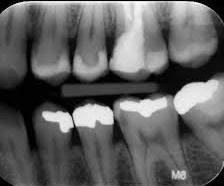

با توجه حضور مسئول ادمین پکس دانشگاه (مورخ 98/7/23 )در دانشکده دندان پزشکی نحوه تبدیل تصاویر تک دندان از فرم آناکوگ به دیجیتال انجام گردید و نحوه ارسال این تصاویر با مشخصات بیمار بر روی سامانه پکس به متخصص محترم رادیولوژی (آقای دکتر فتح الله زاده) و کارشناس محترم رادیولوژی دانشکده دندانپزشکی (خانم مهرآوران) آموزش داده شد. لازم بذکر است این تصاویر قبلا بر روی فیلم رادیوژی ایجاد می گردیده است .